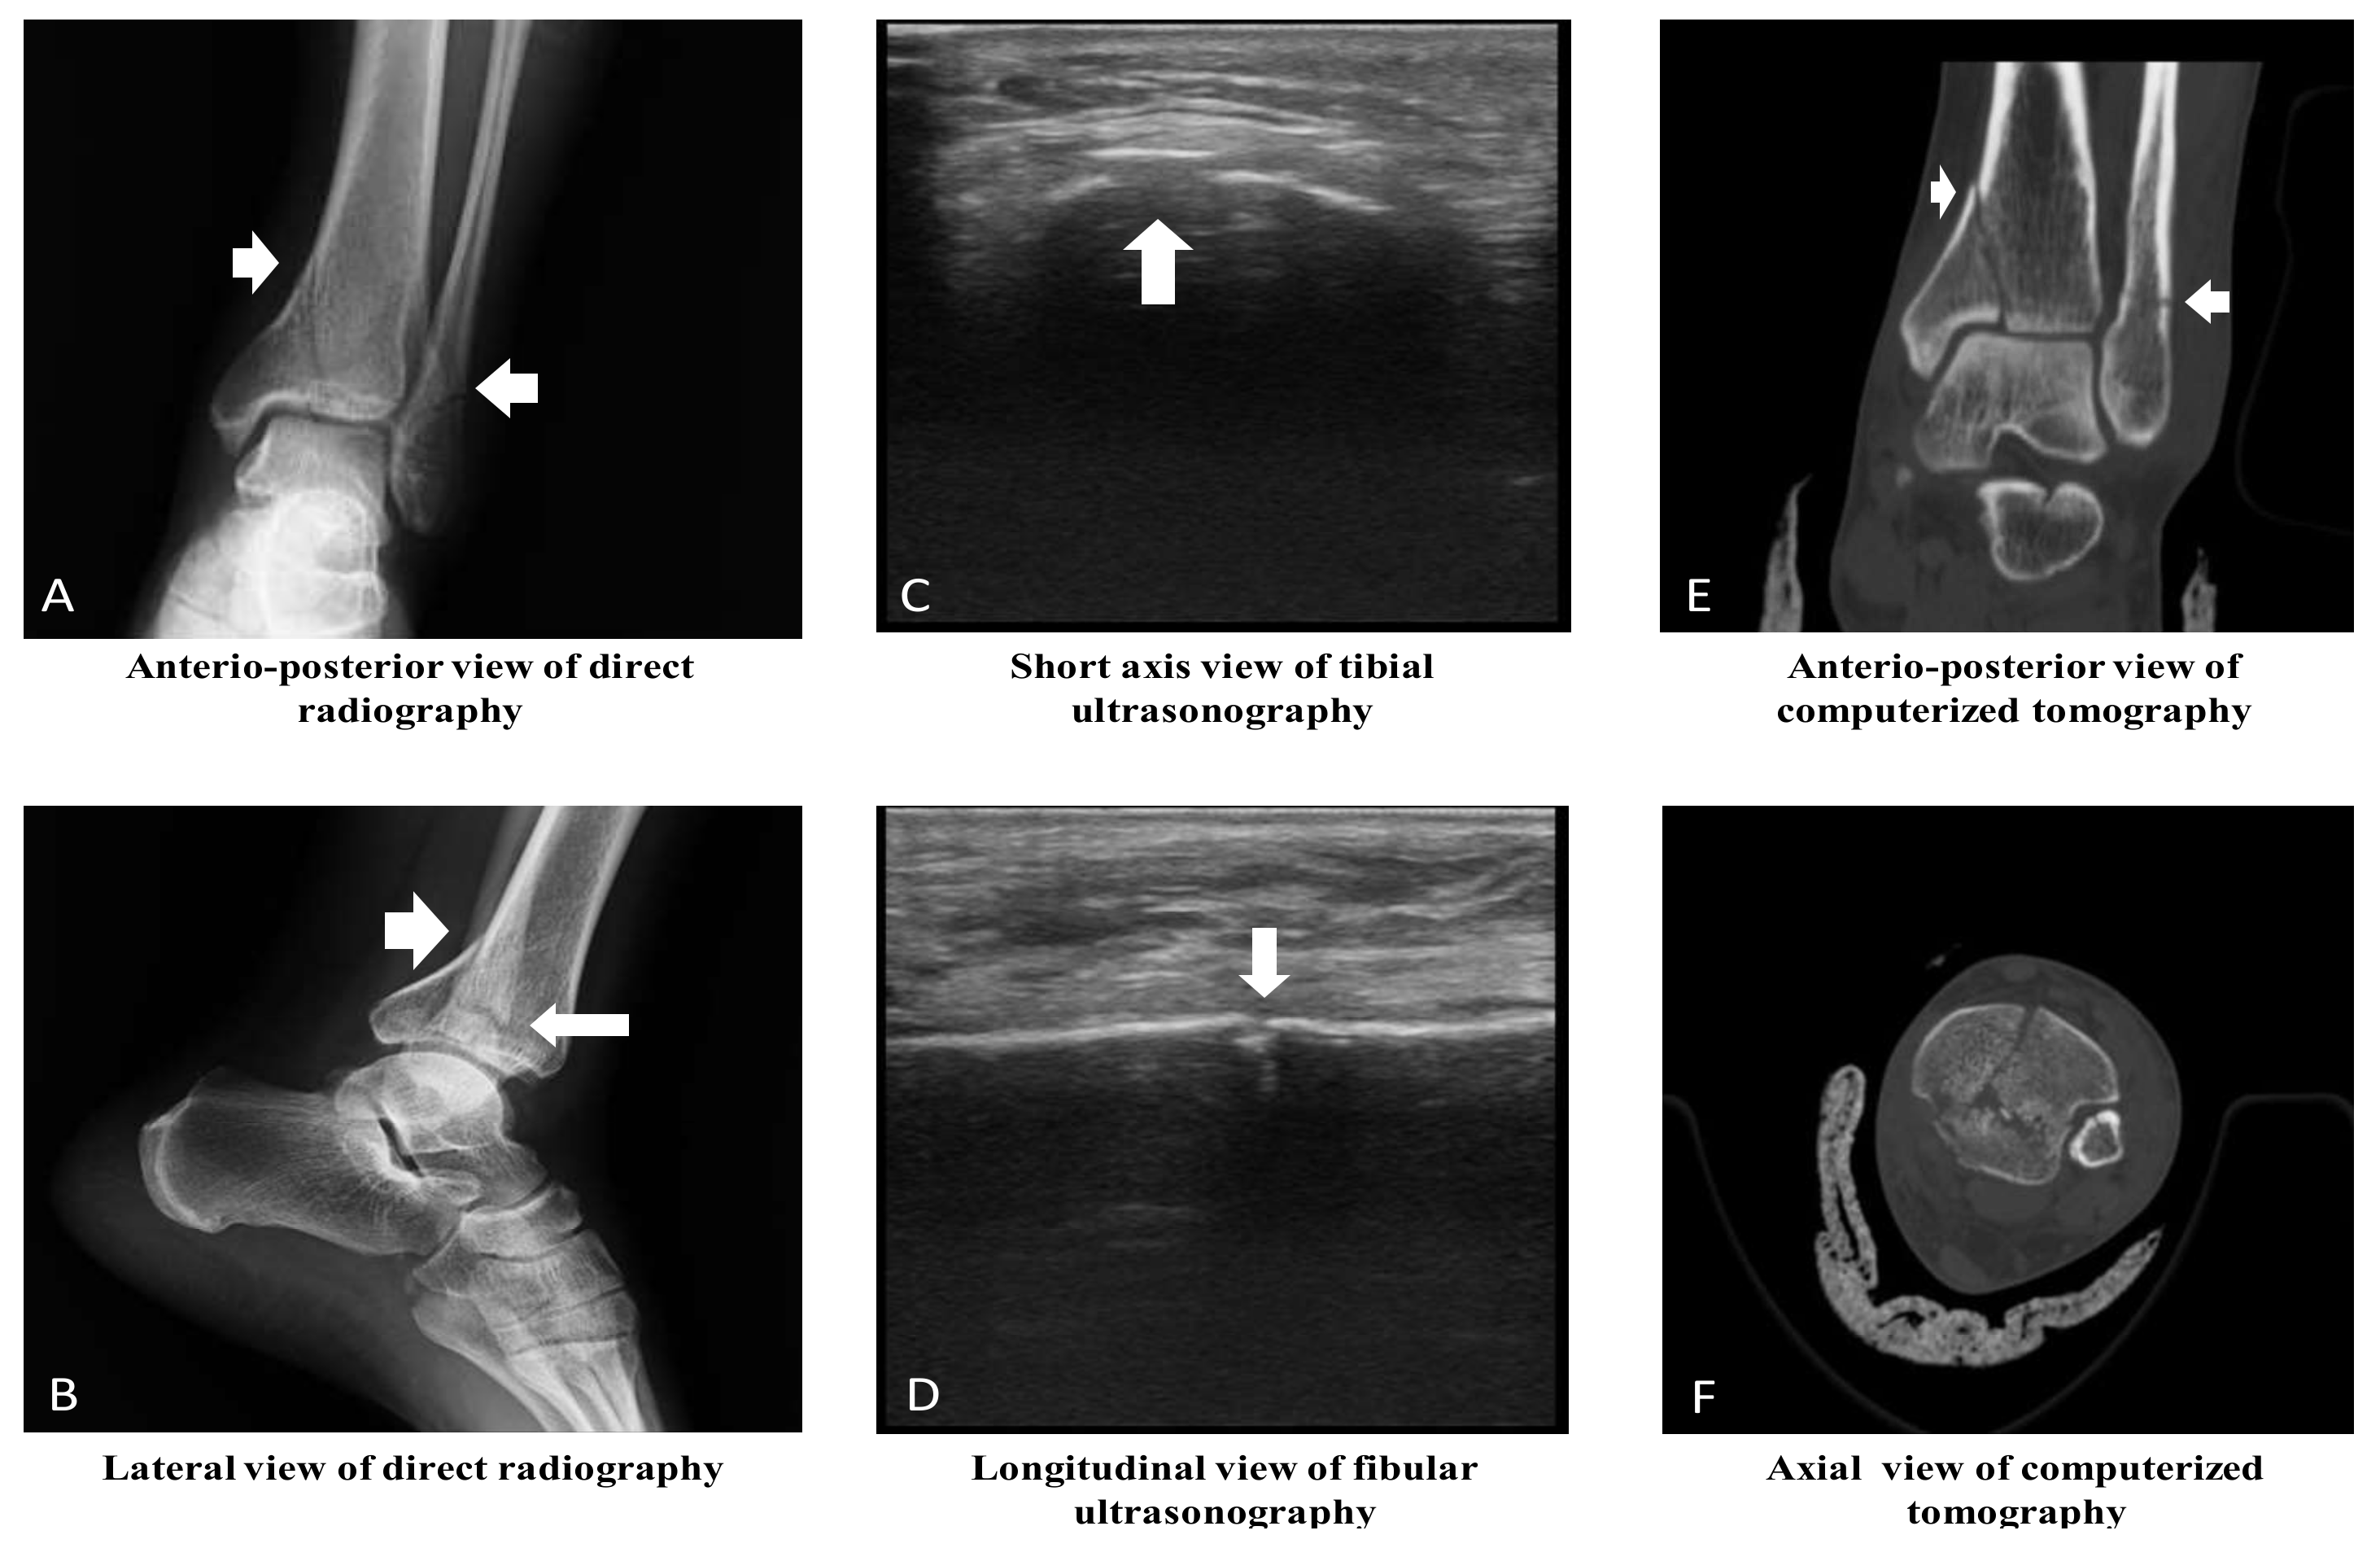

The sensitivity, specificity, PPV, and NPV of POCUS in determining the fractures were 99%, 93%, 93%, and 99%, respectively, compared to XR (p < 0.001, κ: 0.922, AUC: 0. 962, 95%, and CI: 0.932–0.992). The most common fracture type was linear fractures (Table 5, Figure 2, and Supplementary Materials Video S1). Compared to XR, POCUS was able to determine 100% of fissure type fractures (X2, p < 0.001, and κ: 0.765), 83% of linear fractures (X2, p < 0.001, and κ: 0.848), 92% of fragmented fractures(X2, p < 0.001, and κ: 0.756), 67% of spiral fractures (X2, p < 0.001, and κ: 0.798), 75% of avulsion type fractures (X2, p < 0.001, and κ: 0.855), and 100% of full separation type fractures(X2, p < 0.001, and κ: 0.855) (Table 6). According to the κ value, a perfect concordance between POCUS and XR in identifying all types of fractures was determined.

Figure 2.

Radiological images of ankle joint in a 33-year-old male patient. (A) Tibial linear fracture with extension into the joint space and fibular linear fracture. (B) Tibial linear fracture with stepping-off and angulation, and fibular linear fracture. (C) Tibial fragmented fracture with stepping-off and angulation. (D) Fibular linear fracture. (E) Tibial linear fracture with extension into the joint space, and fibular linear fracture. (F) Tibial fragmented fracture, and fibular linear fracture. (Note: The clinical orthopedics and traumatologist thought that computed tomography is required for determining the characteristic of fractures and treatment decision of fractured bones.).

LB fractures were mostly determined at a distal localization (Table 7). The XR images revealed that the fractures extended to the joint space in 15 (7%) patients, the fractures involved the epiphyseal line in 7 (3%) patients, the fractures were angulated in 45 (22%) patients, there was a stepping-off distance of the fracture in 39 (19%) patients, and there were accompanying adjacent bone fractures in 14 (7%) patients. The sensitivity of POCUS was found to be low in determining the fractures extending to the joint space (Table 8). According to the κ value, a perfect concordance between POCUS and XR in angulation (κ: 0.871), stepping off (κ: 0.953), and involvement of the epiphyseal line (κ: 0.921) were determined. This concordance was moderate in the extension of the fracture into the joint space (κ: 0.643).